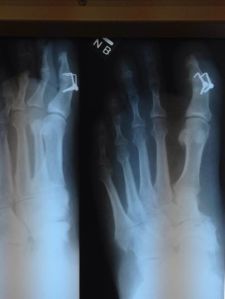

Had a follow up with my surgeon on Tuesday. He took the first post-op x-rays and pronounced everything in order. I see him in two weeks and he said, “Bring a regular shoe with you.”

The x-rays look kind of cool. You can clearly see the plaples (combination of plate and staple) that are holding the tip of my toe onto the rest of my foot. The surgeon told me he went that route because he didn’t want an issue with a screw that might work its way out of the bone. I am appreciative, that’s for sure.